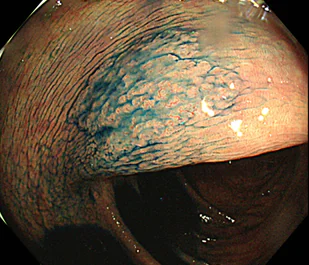

鋸歯状ポリープ

鋸歯状ポリープは、ノコギリの歯のような形状を示す病変の総称です。かつては、がん化しないと考えられていましたが、近年の研究により、その一部から大腸がんが発生することが明らかになってきました。右の写真に示すのは、鋸歯状病変の一種である「無茎性鋸歯状腺腫」です。主に大腸の右側に生じやすく、周囲と同じ色調またはやや褪色した色合いを示す、比較的平坦なポリープとして認められます。